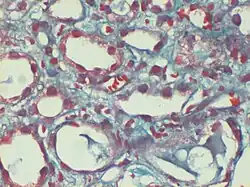

Trichrom-Färbung

Die Trichrom-Färbung ist eine Methode zur Färbung von Zellen und Geweben mit drei Farbstoffen (Chromophoren).